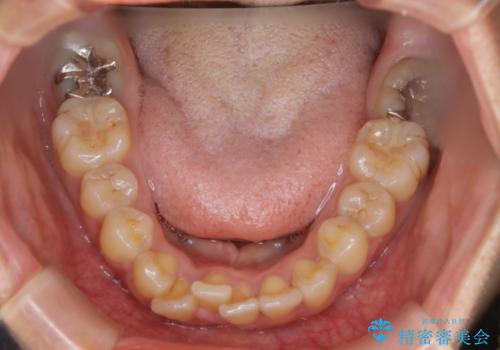

前歯を後ろに下げたい ワイヤー矯正(クリア装置)

- 前歯を後ろへ下げることを主訴に来院された患者様です。

10代の時に非抜歯でワイヤー矯正をしていました。

口元の突出感の改善や歯の移動量などを考慮し、抜歯を伴うワイヤー矯正での治療を選択しました。

抜歯を行うことで前歯を後ろへ下げるスペースを獲得し、口元の突出感や歯のガタつきを改善していきました。